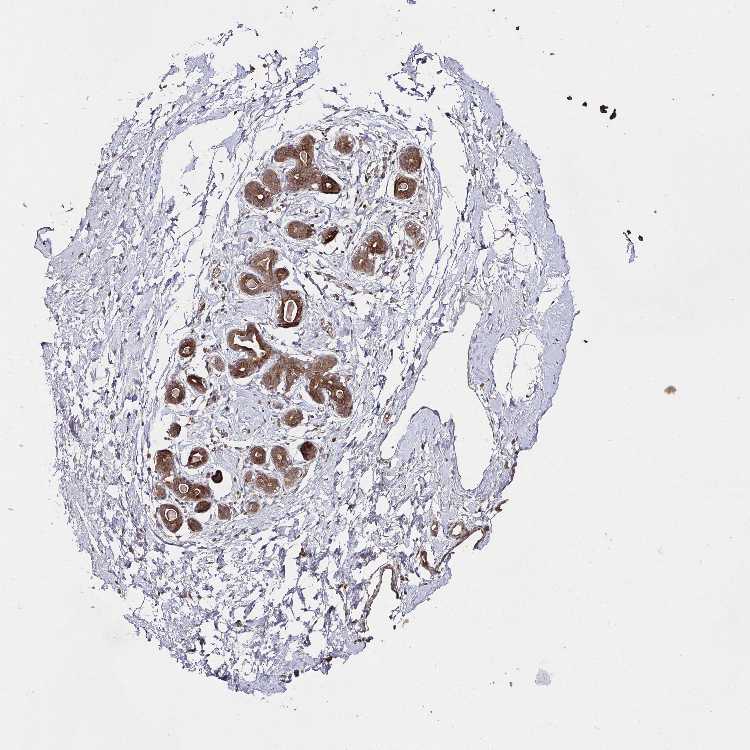

BREAST - Antibody stainingi

Antibody staining in the annotated cell types in the current human tissue is reported as not detected, low, medium, or high, based on conventional immunohistochemistry profiling in selected tissues. This score is based on the combination of the staining intensity and fraction of stained cells.

Each image is clickable and will lead to virtual microscopy that enables deeper exploration of all samples and also displays staining intensity scores, fraction scores and subcellular localization as well as patient and tissue information for each sample.

Antibody HPA045821Antibody HPA054352Antibody CAB012229

Glandular cells MediumHighHigh